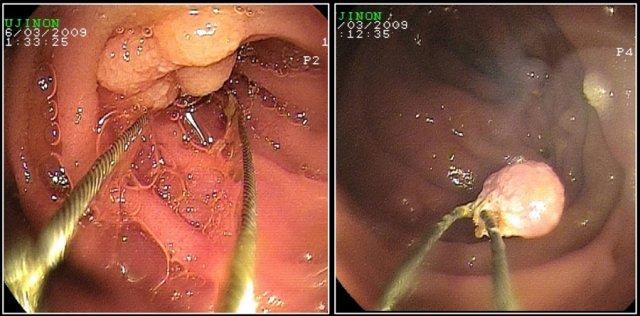

Đây là hình ảnh nội soi của khối u.

Đây là bệnh nhân có dày thành lan rộng ở đoạn gần hỗng tràng kèm giãn phình dạng túi phình.

Chẩn đoán hàng đầu trong danh sách chẩn đoán phân biệt của chúng tôi là u lympho, nhưng kết quả giải phẫu bệnh xác nhận là ung thư biểu mô tuyến.

Các đặc điểm gợi ý ung thư biểu mô tuyến là thâm nhiễm mỡ mạc treo (fat stranding) và di căn hạch bạch huyết.

Trong u lympho, thâm nhiễm mỡ ít gặp, nhưng di căn hạch bạch huyết vẫn xảy ra và thường có kích thước lớn hơn.